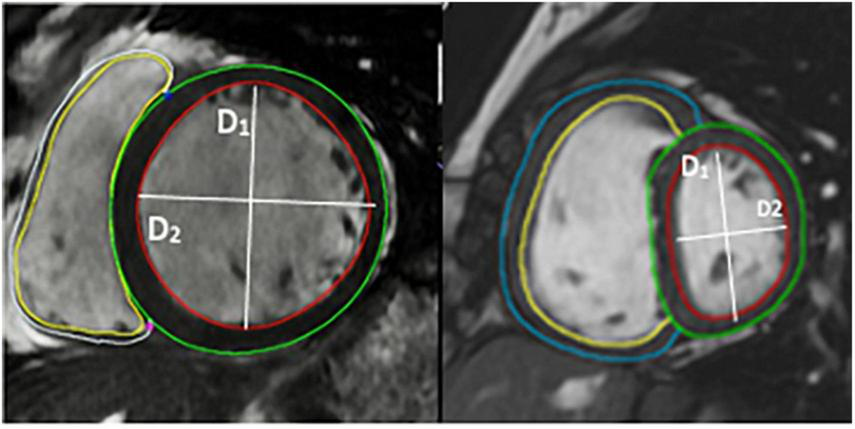

Cardiac magnetic resonance imaging was performed using a 1.5-T magnetic resonance imaging scanner (Sonata Magnetom, Siemens, Erlangen, Germany) in the headfirst supine position, with gated cardiac synchronization. Initial scout images were acquired using fast imaging with steady state precession. Vertical and horizontal long axis cines were planned and acquired based on the scout images. The short axis images were then planned from the horizontal long axis views. RV and LV volumes were determined by automatic tracing of endocardial borders of the short axis stack using Circle Cardiovascular imaging software (Calgary, Canada). All borders were manually verified and corrected as needed. Main pulmonary artery flow curve was captured using velocity-encoded (VENC) CMR, perpendicular to the pulmonary artery. A VENC of 100 cm/s was used for image acquisition. EI was measured at end systole and end diastole in both left and right ventricles (RV) at mid-ventricular level—defined as the level of the papillary muscles. The EI is defined as the ratio of the length of the two perpendicular minor-axis diameters, one of which is bisected and was perpendicular to the interventricular septum (Figures 2, 3). The ratio of the minor axis dimensions was measured, D2/D1, where D1 is ventricular diameter perpendicular to the septum and D2 is ventricular diameter parallel to the septum. In the absence of RV pressure overload, the LV is circular, and D2/D1 would be expected to be 1.0 (13). Main pulmonary artery distensibility was determined using VENC images with luminal area measurements at the moment of maximal flow and the moment of isovolumetric contraction to calculate the ratio of (PA maximum area–PA minimum area)/PA minimum area. Flow curves were generated using the VE-CMR images obtained perpendicular to the pulmonary artery during breath hold.

Image of short axis CMR demonstrating the volumetric analysis and the calculation of eccentricity index using CMR images.

D1 is the endocardial measurement perpendicular to the interventricular septum at the largest diameter. D2 is the endocardial measurement at the largest length. D2/D1 is used to calculate eccentricity index in end-diastole and end-systole. These can be difficult to define in pulmonary hypertension, so, using the QRD complex to identify systole, images were identified around the end of systole and the end diastole. These were analyzed and those with the smallest LV volume were classed as end-systole and those with the largest were classed as end-diastole.